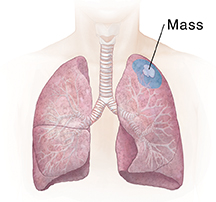

| Wedge resection removes a small part of a lobe. |

A lung mass or tumor

If a tumor has been found in the lung, a tissue sample (biopsy) can be removed. This piece of abnormal tissue is tested in a lab to find out if the growth is not cancer (benign) or is cancer (malignant). The tissue near the tumor can also be examined to see if the tumor has spread. If the tumor needs to be removed, its size, location, and spread determine how much of the nearby lung also needs to be removed. Removing part or all of a lung is called a lung resection.